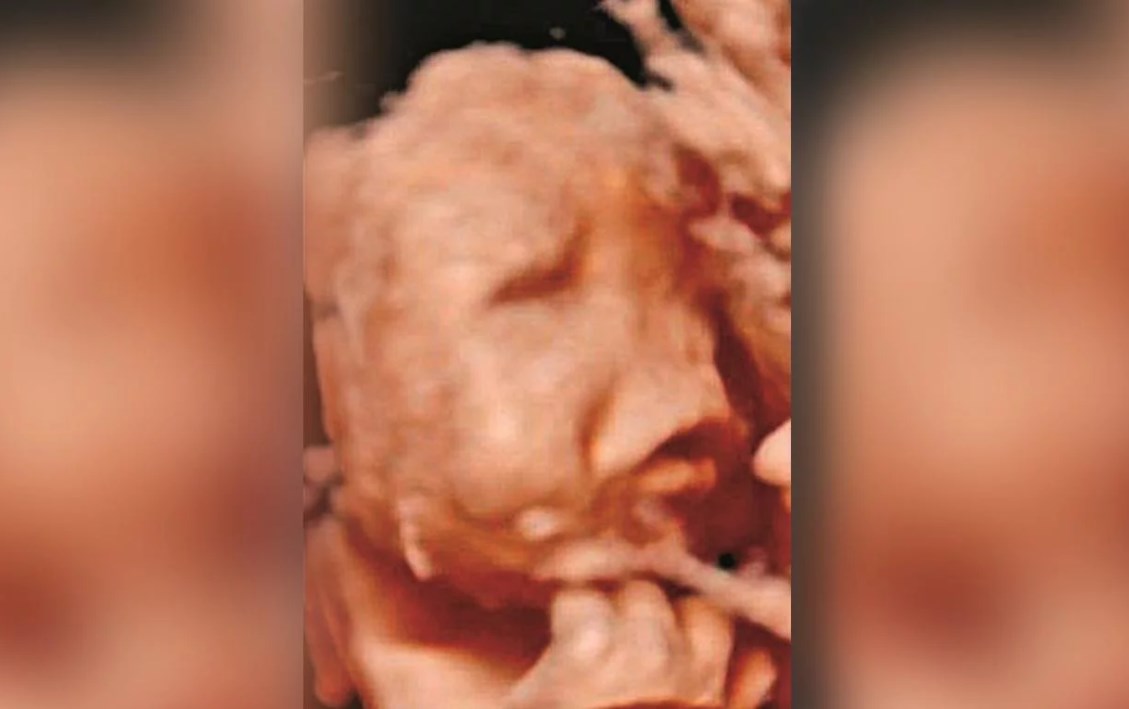

El programa Rua segura, de Correio da Manha, brindó una entrevista a la familia y la primera foto de la criatura, en la que se lo puede ver junto a su hermana mayor. También mostró postales con sus padres e, incluso, una de las polémicas ecografías.

Durante la entrevista, los padres de Rodrigo mostraron uno de los ultrasonidos que les hizo el obstetra Artur Carvallo, que los atendió durante todo el embarazo y que jamás se dio cuenta de las malformaciones en el feto.

Pero como si eso fuera poco, el médico desestimó una cuarta en 5D que la madre se había hecho en otro centro médico y en la que sí les alertaron que algo no andaba bien.